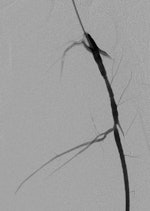

Doctors involved in the care of these patients need to understand the patterns and mechanisms of the injuries, he explained. To accurately interpret images of gunshot wounds, a basic knowledge of ballistics is important, especially the factors affecting the extent and type of tissue damage. Such knowledge is useful not only for evaluating acute injuries but also for determining the path of the missile, awareness of missile fragmentation, and embolization, thus contributing to the overall clinical, and often the forensic, picture.

Gunshot wounds inflicted by handguns are usually classified as low-velocity injuries, having a muzzle velocity less than 600 m/sec, stated Shawyer. In addition to missile velocity, the amount of tissue damage depends on factors such as the design of the projectile (e.g., full metal jacket, soft point, hollow point), biological tissue characteristics, the entrance profile/angle of the projectile when it goes into the body, and the caliber of the projectile.

The two mechanisms of tissue injury that account for the majority of damage caused by a bullet are direct crushing of tissue by the projectile (causing a permanent cavity) and temporary cavitation, which stretches and tears surrounding tissues. Increased velocity, fragmentation, deformation, and rolling/spinning of the bullet will cause more damage by both these mechanisms, he pointed out.